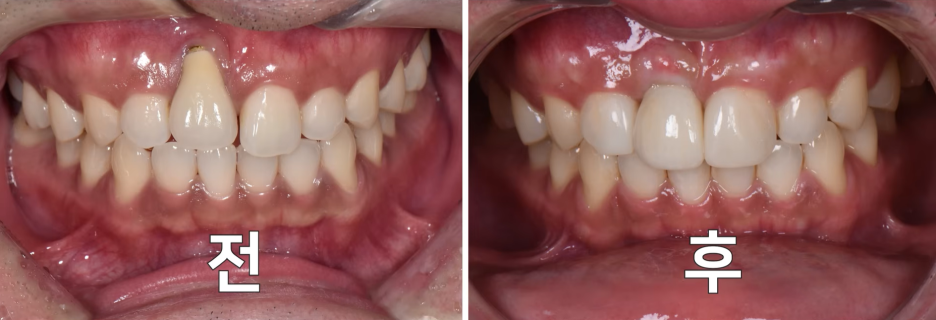

아이낳고 잇몸이 내려 앉았는데 40대 후반이 되니깐 잇몸이 더 내려갔어요

출처 - 권의 시선 : 치과의사 권낙현 유튜브  (교정이 잘못되어 내려앉은 경우)

출처 - 권의시선 : 치과의사 권낙현 유튜브  CTG(결합조직이식술)-입천장에서 결합조직을 채취하여 내려앉은 잇몸에 이식하는 치료방식

출처 - 권의시선 : 치과의사 권낙현 유튜브  입천장에서 채취한 조직을 내려앉은 부위에 붙인 모습.

출처 - 권의시선 : 치과의사 권낙현 유튜브  수술후 실로 단단히 고정한 모습

출처 - 권의시선 : 치과의사 권낙현 유튜브